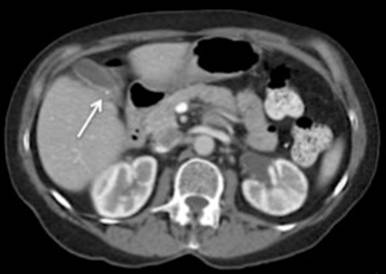

A 72-year-old woman presented with right upper quadrant pain, nausea, and fatigue for the last six months. She underwent an abdominal ultrasound and CT scan that demonstrated a 1 cm thickening of the posterior gallbladder wall and a 2 mm associated punctate calcification (Figure 1). CEA and CA 19-9 levels were normal. She was referred to our center for consideration for radical cholecystectomy and central hepatectomy for a suspicion of gallbladder cancer.

Figure 1. CT scan showing punctate calcification within the thickened posterior wall of the gallbladder (arrow). |